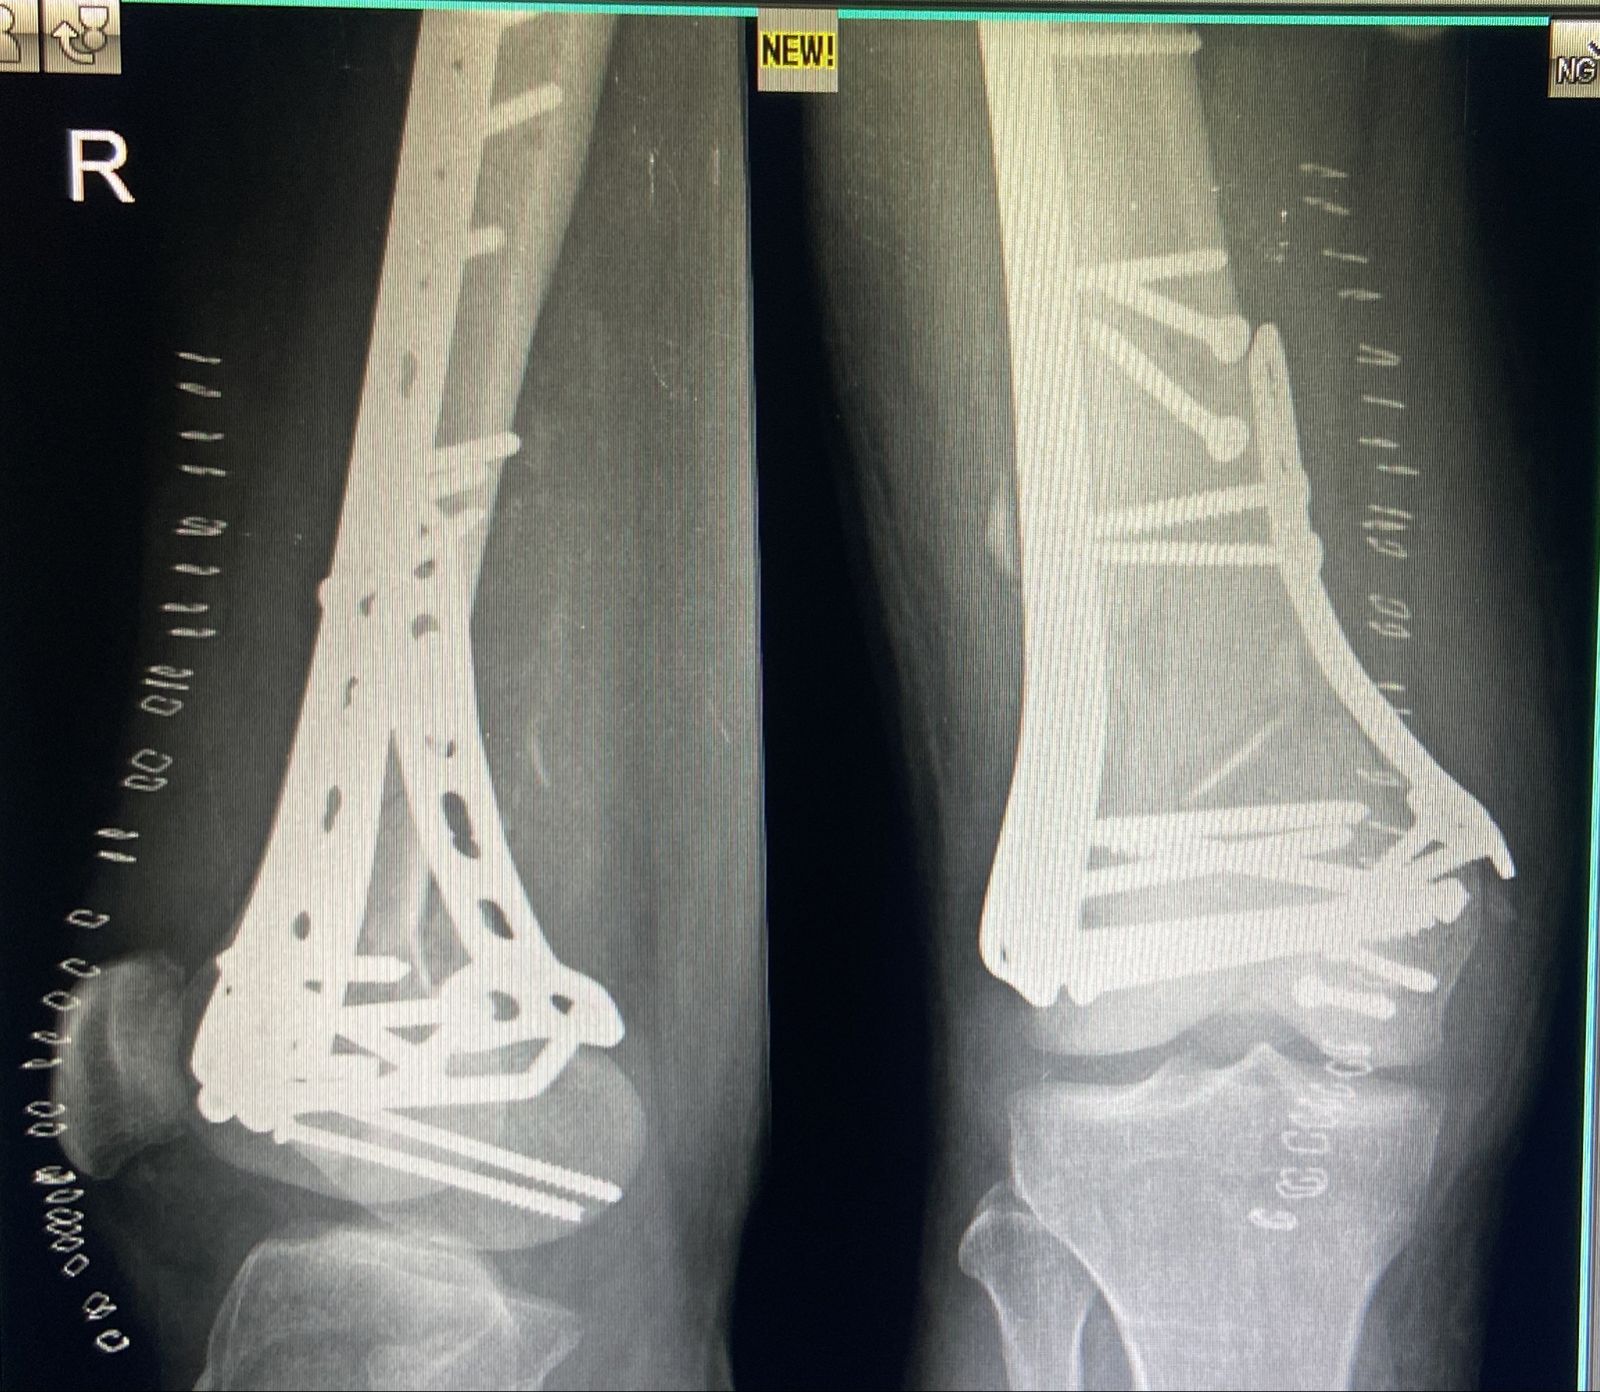

The smaller bone fragments are aligned with metal wires or screws. When the end of broken bones settles, the area is kept stiff with a plaster cast, splint and brace. Also some implanted electrical devices that stimulates have proved to be helpful in curing the fracture where the fracture repair is not possible in other means.

Dr. Hardik Shah has performed 1000+ Trauma and Orthopedics surgeries applying the means of traction and/or by immobilization of the bones for fracture repairs. The bone fragments are aligned as closely as possible to their normal position without injuring the skin. Metal wires or screws may be needed to align smaller bone fragments. Once the broken ends of the bone are set, the affected area is immobilized for several weeks and kept rigid with a sling, plaster cast, brace, or splint. With the use of traction, muscles pulling on the fracture site are neutralized by weights attached to a series of ropes running over pulleys. Strategically implanted electrical stimulation devices have proven beneficial in healing a fracture site, especially when the fracture is healing poorly and repair by other means is difficult.